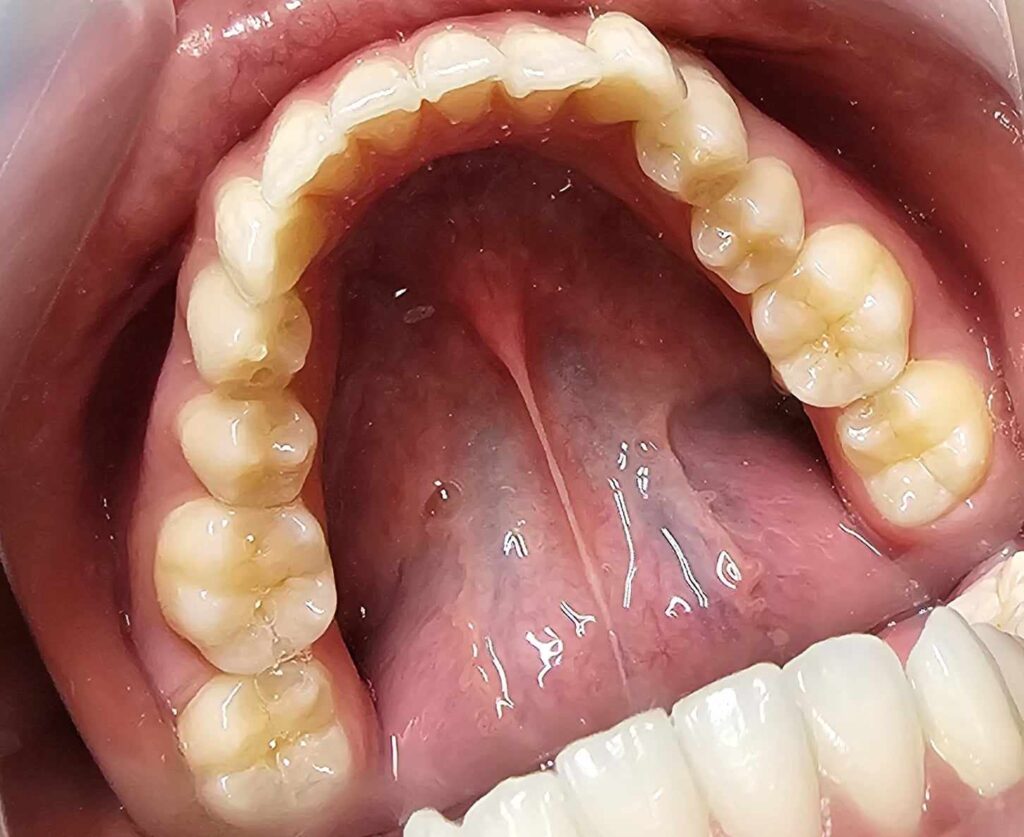

治療前

- 初診:2016年、9歳女児

- 主訴:出っ歯と歯の隙間がきになる。

- 診断:2級過蓋咬合、上下永久歯(犬歯)萌出スペース不足

- 治療方針:非抜歯で行う。虫歯予防(フッ素)、歯磨き指導、上下拡大床→咬合関係改善のツインブロック(2級→1級関係へ)→マウスピース矯正→下親知らずの抜歯、保定→メンテナンス